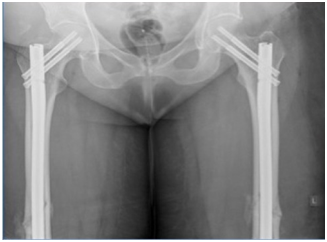

A 71 year old post menopausal Caucasian woman with elevated BMI of 34 & NIDDM, presented to the emergency department with acute severe bilateral thigh pain and inability to weight bear following a low impact fall from standing height. She also complained of an 18 month history of bilateral thigh, groin & back pain, for which she was diagnosed with “fibromyalgia”. She had been taking ibandronic acid 150mg by mouth monthly for the last 5 years for the treatment of postmenopausal osteoporosis. Plain radiographs of both limbs revealed a displaced fracture in mid-shaft region of both femori (Figure 1). Ibandronic acid was stopped and the patient underwent internal fixation with bilateral intramedullary reconstruction nails, locked proximally and distally (Figures 2 & 3). The patient made uneventful post-operative recovery and was subsequently discharged with outpatient follow-up.

Figure 2 Post operative images.

Figure 3 Post operative images.